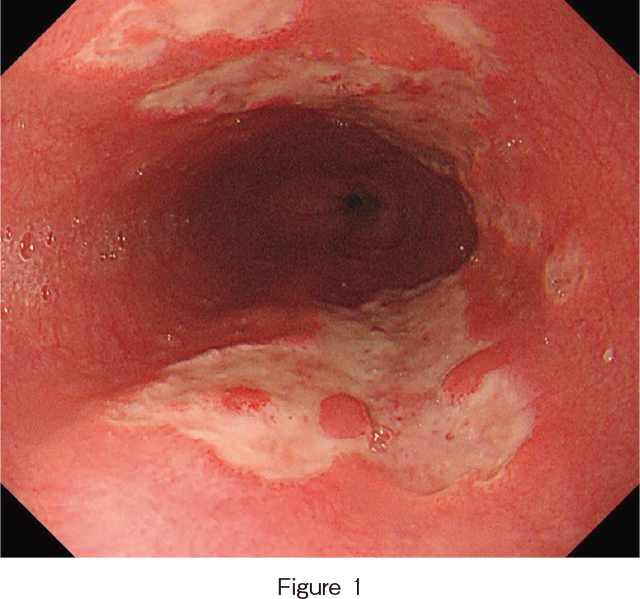

上部消化管内視鏡所見(入院翌日):胸部中部食道に辺縁明瞭な地図状潰瘍を認め,潰瘍は腹側と背側に多発していた(Figure 1,2).

通常光観察では,中部食道に辺縁明瞭な大小不同の不整形潰瘍が背側・腹側に多発している.

狭帯域光観察では,潰瘍辺縁粘膜の表面に明らかな粘膜構造および血管構造の不整は認めなかった.